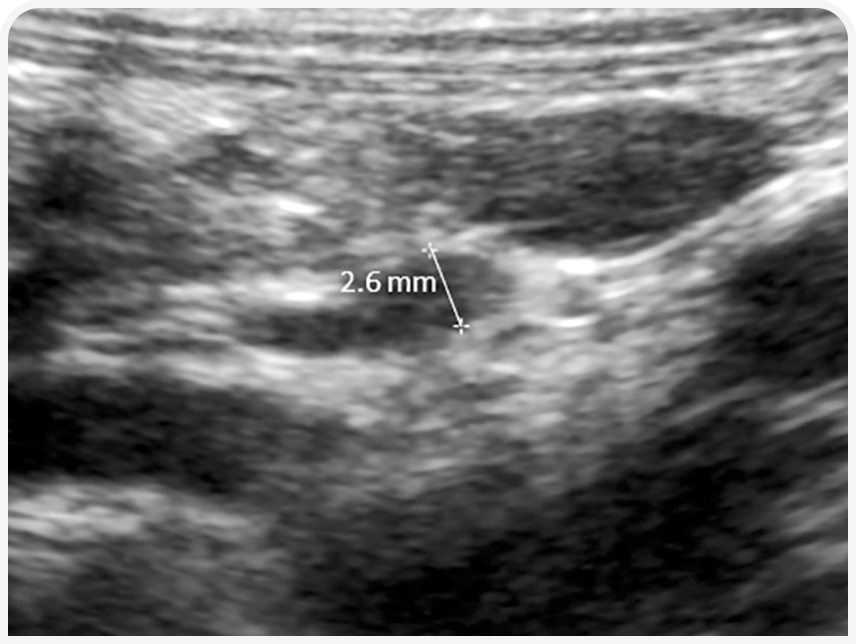

Ультразвуковое исследование органов брюшной полости с тщательной оценкой обоих надпочечников часто также не информативно, но иногда диаметр надпочечников уменьшен, что позволяет заподозрить гипоадренокортицизм (Рисунок 4). Ультразвуковое исследование также показано в подозрительных случаях для диагностики или исключения новообразований, инфаркта или кровоизлияния в надпочечники (1).